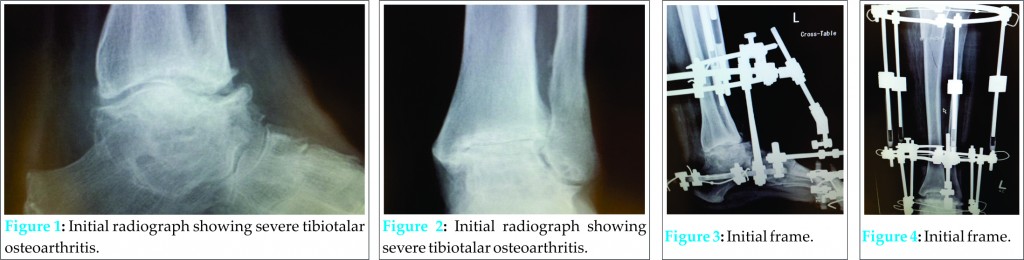

A 67 year old Caucasian woman with a history of epilepsy was admitted for complex reconstruction of the lower limb, secondary to spastic cerebral palsy. Five centimetres of true shortening in the tibia were associated with midfoot and hindfoot deformities and severe tibio-talar osteoarthritis (Figs 1 and 2). A multifocal Ilizarov circular frame was constructed, with a proximal lengthening segment to address limb length inequality; a hindfoot segment to perform tibiotalar arthrodesis for severe degeneration and a forefoot segment to achieve acute derotational correction of a midfoot deformity (Figs 3 and 4). The post-surgical period was complicated by an episode of respiratory embarrassment due to pneumonia which required short term ventilation. Subsequent recovery appeared to have occurred, and the patient and her husband were formally instructed in the correct method and rate of adjustment to achieve proximal lengthening.

The patient failed to attend for regular follow-up, and represented at six months following index surgery complaining of worsening deformity. On examination, the proximal threaded rods of the circular fixator were bent and severe valgus deformity was apparent within both the frame and the limb. On questioning, it became apparent that the patient’s husband had been lengthening the medial aspect of the frame and compressing the lateral aspect. At this juncture, the regenerate, midfoot and hindfoot arthrodeses were deemed consolidated (figs 5-7), and the patient refused further frame treatment to correct the inadvertent proximal tibial deformity. Due to severely symptomatic pre-existing osteoarthritis of the knee, and a prior plan to perform total knee arthroplasty at a later juncture, a single stage intervention was proposed, utilising a stemmed total knee replacement and a simultaneous closing wedge osteotomy of the tibia to correct deformity and provide primary stability. At surgery, a standard medial parapatellar approach to the knee was performed, and the incision carried distally to the level of the metaphysis of the tibia. Due to severe intra-articular contracture, an extensile approach was performed via an osteotomy of the tibial tuberosity [5]. Standard femoral preparation was carried out. A separate lateral incision was used to perform a fibular osteotomy. An acute closing wedge osteotomy of the tibia was performed and the tibia realigned. Utilising intramedullary guidance, the tibia was prepared appropriately, and a tibial component with a canal filling stem used to bridge the osteotomy, correcting the deformity and simultaneously compressing the osteotomy (Figs 8 and 9). The tibial tuberosity was reattached with a large fragment screw. Uneventful osteotomy union subsequently occurred by three months post-operatively (Fig 10). Knee range of motion at final follow-up was 0-5-105 and no instability was reported by the patient.